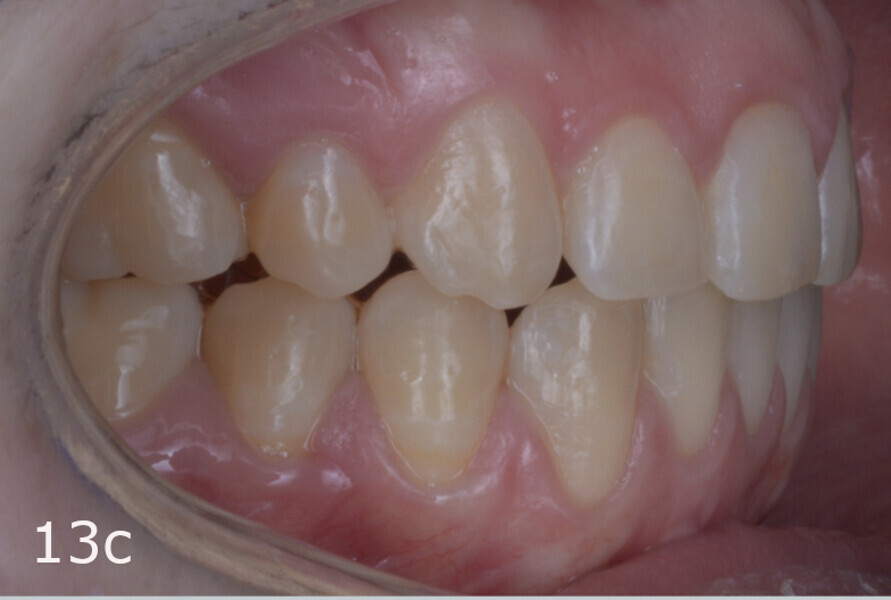

The treatment objectives included closing the anterior open bite, achieving a bilateral Angle Class I relationship and a proper overjet and overbite, correcting the midline discrepancies, and achieving a profile harmonisation. The treatment plan consisted of orthodontic camouflage treatment with asymmetric distalisation in three of the four quadrants using Invisalign aligners (Align Technology) and third molar extraction. The Invisalign Comprehensive package was chosen, and 63 pairs of aligners were used (Figs. 7–10). Each aligner was worn for 20 hours a day for one week each. The use of Class III elastics on both sides was indicated. Afterwards, ten refinement aligners were needed to improve the interdigitation on the right side (Figs. 11 & 12).

The total treatment time was 15 months. An Angle Class I relationship was established along with adequate anterior and canine guidance, establishing a functional occlusion. This not only ensures optimal masticatory function but also protects the teeth and the temporomandibular joint from excessive force. Maxillary and mandibular fixed retention were installed at the end of the treatment (Figs. 13–19).